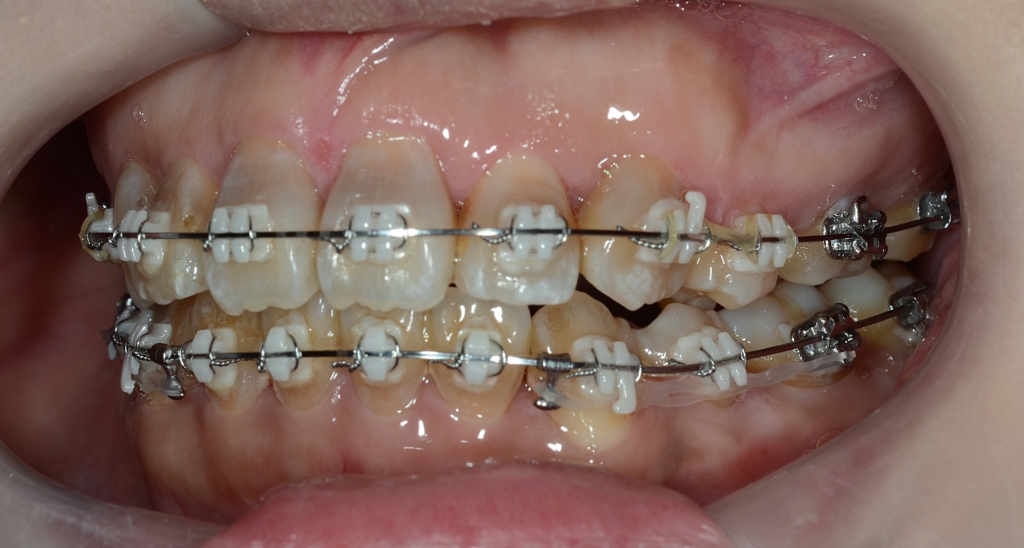

マルチブラケットシステム(スタンダード type)で矯正を開始。

先ず、上下とも前歯の凸凹の歯並び(叢生)の解消を図ります。

その後、前歯がきれいに並んだら、可及的に奥へ引っ込めながら残る隙間をなくしていきます。